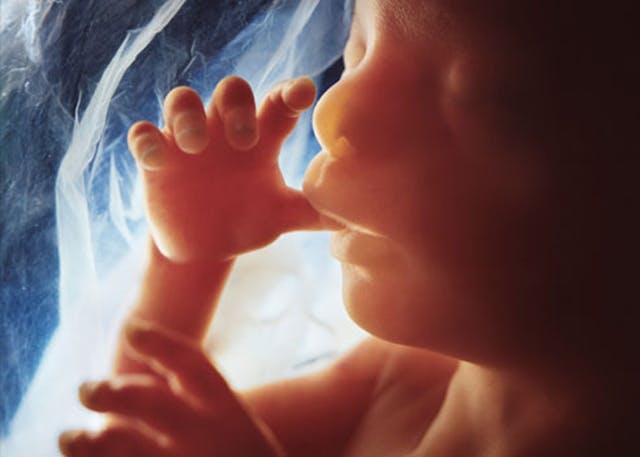

At 20 weeks, pain receptors are present throughout the baby’s body, and nerves are able to link these receptors to the baby’s brain. The baby can be seen reacting to stimuli that could be recognized as painful, by doing things like recoiling. Increases in stress hormones can be seen when the baby experiences painful stimuli. And while the abortion lobby tries hard to dismiss this as junk science, the reality is that it is just the opposite. In fact, doctors who perform fetal surgery use anesthesia on a routine basis – why would this be necessary if the baby could not feel pain?

The vast majority of people recognize the humanity of the preborn baby at 20 weeks. By 20 weeks, the baby can hear noises and recognize his mother’s voice. The baby will actually react to loud sounds, and noises that she becomes accustomed to hearing in the womb will be soothing to her when she is born. Other sensory development takes place as well – all five senses are being developed in the baby’s brain. And by 20 weeks, most women have already been able to feel their baby kicking and moving. The baby has also started swallowing, and her body begins producing meconium.

One additional week may not seem to make a big difference, but a week can do a lot during pregnancy. At 21 weeks, the baby is making blood cells and their small intestine begins absorbing sugars that they gain from swallowing amniotic fluid. The baby’s taste buds have begun developing too, and she will start to learn what kinds of foods she likes or dislikes, thanks to the changing taste of the amniotic fluid, which is influenced by what her mother is eating.